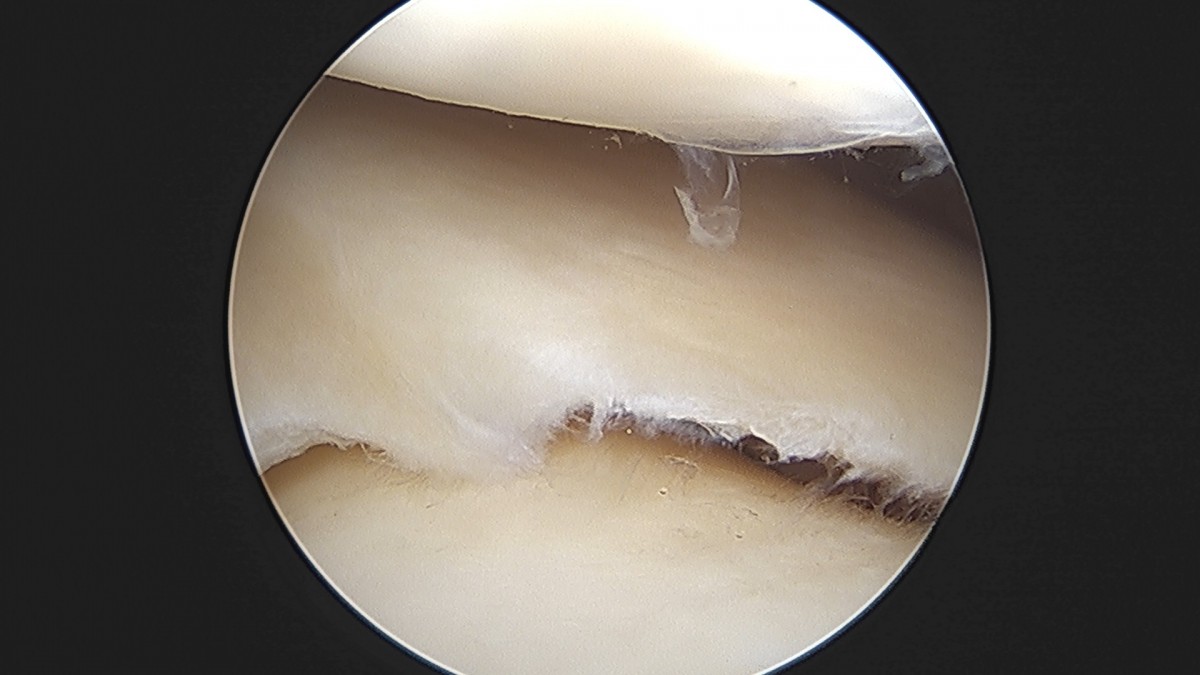

이재상원장님 무릎 반월상 연골판 절제술 박강O 환자

작성자 최고관리자 댓글 0건 조회 381회 작성일 25-09-16 15:47